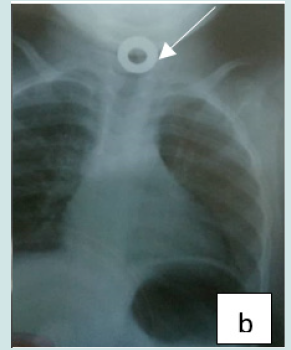

Cervico-thoracic X-ray performed in 211 cases (99%) showed opacity in 209 cases (99%). In one case, 2 circular opacities were observed, one of which had a double contour, indicating the ingestion of 2 foreign bodies (Figure 1: a, b, c, d, e, f). Foreign objects were a coin in 182 cases (85.4%), a shirt button in 4 cases (1.88%), a food in 7 cases (3.27%), and a flat battery in 3 cases (1.41%) (Table III). In 2 cases (1%) the EC was radiolucent.

Figure 2: b: Circular esophageal CE of metallic tone, round opacity with an opening (metallic toy piece).